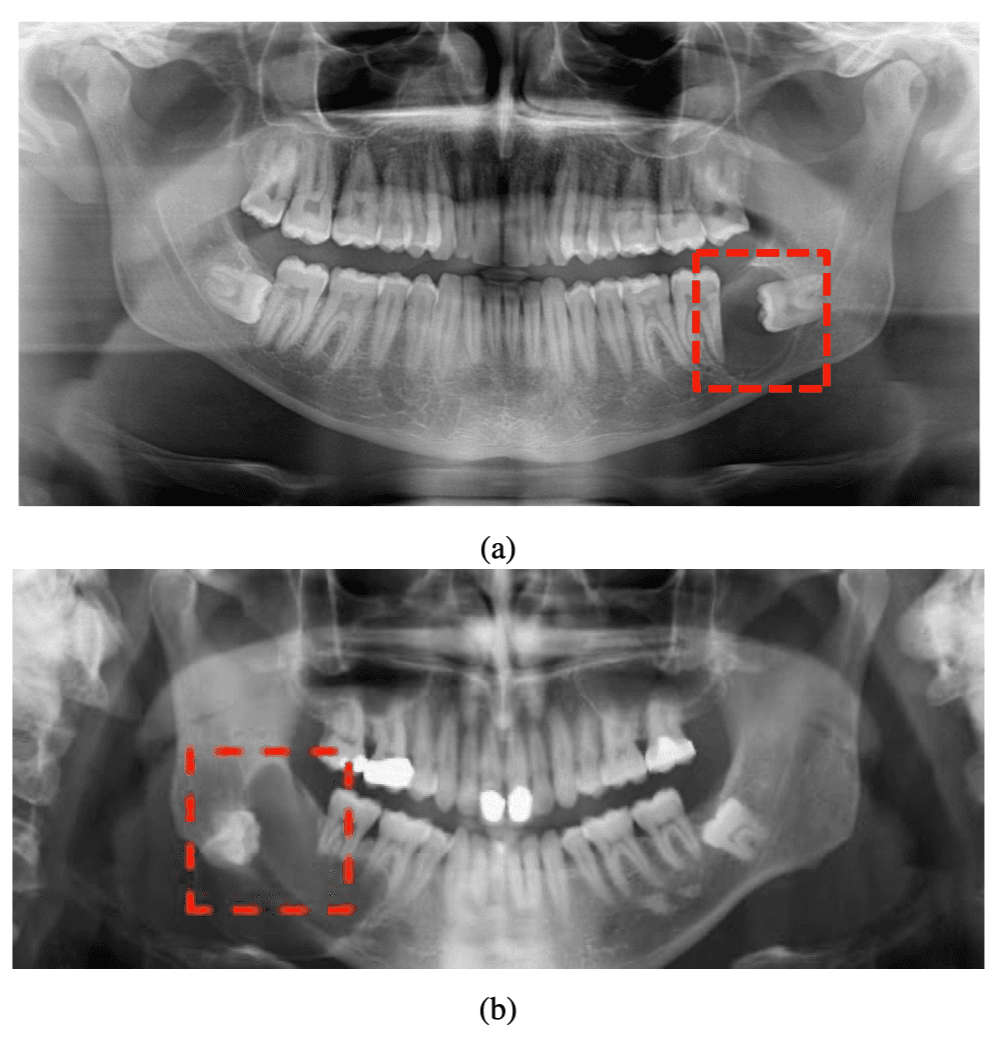

Hybrid Attention Vision Transformer for Dentigerous Cyst Detection (HA-ViT)

- Proposed a hybrid ViT pipeline for dentigerous cyst detection in panoramic dental radiography using dual-path learning (global image + lesion-focused region), achieving 94.44% accuracy, 90.64% sensitivity, 96.74% specificity, and AUC-ROC 0.9829.

Hybrid Vision Transformer for Detection of Dentigerous Cysts in Dental Radiography Images